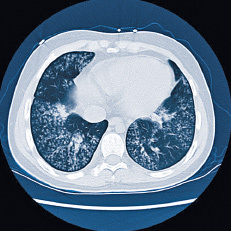

Abb.1

HR-CT Bild eines sternförmigen Lungenkarzinoms.